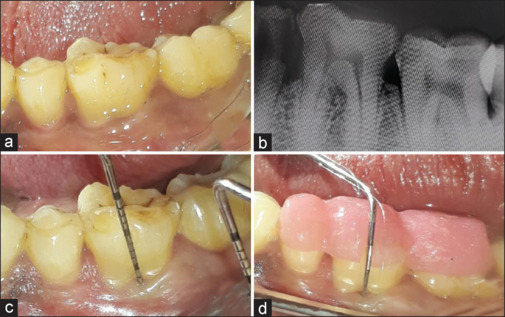

Materials and methods: The present study was a split-mouth design, in which a total of thirty patients with bilateral grade II furcation defects in the mandibular molars were selected. On the control side, the furcation defect was treated using only HA bone graft and in the test side, the furcation defect was treated using a combination of HA bone graft and PRF as barrier membrane. The clinical and radiological parameters were recorded presurgically, postsurgical at 3 and 6 months, respectively, and the results were statistically analyzed and compared.

Results: The furcation defects treated in the test side showed better healing and bone fill when compared to control side. The clinical parameters of the test and control sides when compared were found to be statistically significant.